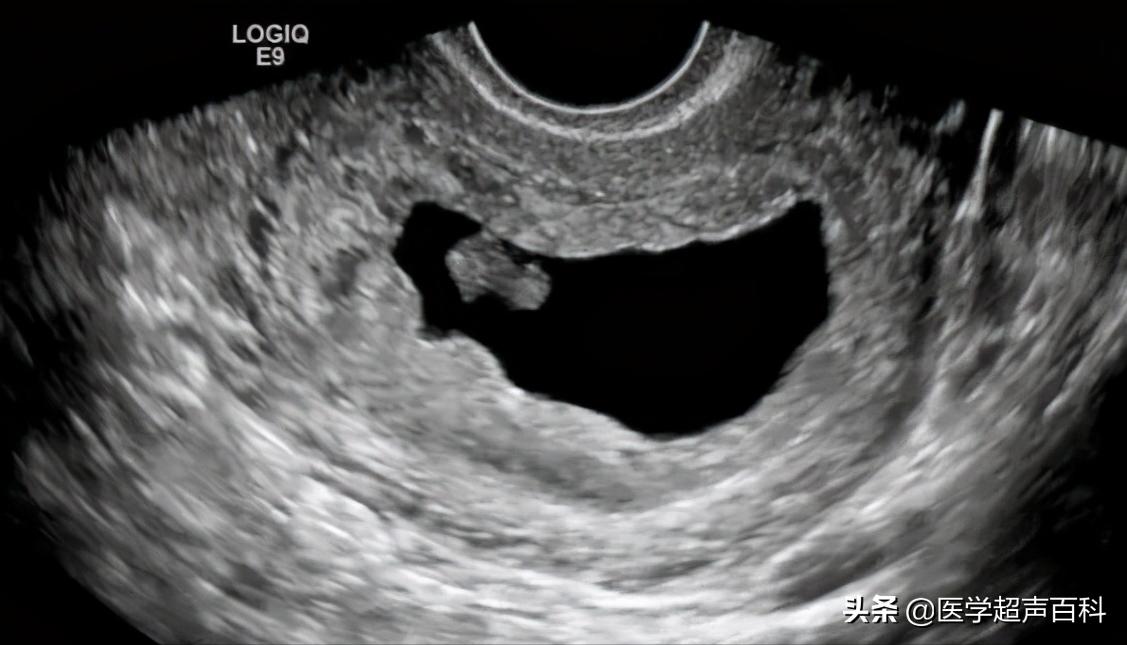

1、空孕囊是指受精卵着床后发育异常,尚未形成胚胎就停止发育。B超:宫腔内只有孕囊而无胚芽策划的异常妊娠。有时B超会描述只见液性暗区,内未见卵黄囊或胚芽。

2、有胚芽无胎心B超示妊娠囊内可见胚芽,但无胎心搏动。

3、有胎心后停育是指B超在动态监测妊娠囊,可以先有胎芽胎心搏动,待一段时间 B超又未监测到胎心搏动,只见枯萎的妊娠囊。

1、胚胎长度≤5mm,无心管搏动,7-10天后复查仍无心管搏动。

2、胚胎长度>5mm,无心管搏动或妊娠囊平均内径>20mm,无卵黄囊及胚胎。

3、妊娠囊平均内径≤20mm,无卵黄囊及胚胎,1-2周后复查仍无卵黄囊及胚胎。

可见胚胎停育是B超医生的描述术语,因为通过B超可以非常直观地看到正常胚胎的胎心搏动和胚胎停育中的无胎心搏动,因为通俗易懂,被患者及医生广泛接受。